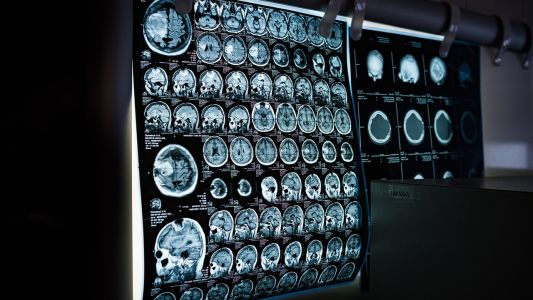

Nudi i napredne dijagnostičke mogućnosti kao što su rendgen, ultrazvuk, CT i MRI, omogućavajući sveobuhvatnu dijagnostiku i efikasan tretman.

Klinika Balkan Medica pruža bezbolno i precizno snimanje magnetnom rezonancom savremenom opremom, uz stručan nadzor i pažljiv pristup pacijentu tokom cele procedure i pripreme.

U klinici Balkan Medica vrši se snimanje abdomena magnetnom rezonancom uz stručan nadzor, savremenu opremu i punu podršku pacijentima tokom celog procesa.

Klinika Balkan Medica nudi uslugu magnetne rezonance glave koja koristi naprednu tehnologiju bez jonizujućeg zračenja. Detaljno pregledamo moguće promene u mozgu i okolnim strukturama, pružajući tačne...

Magnetna rezonanca karlice u klinici Balkan Medica obavlja se u prijatnom i profesionalnom okruženju, uz iskusne lekare koji osiguravaju sigurnost i udobnost pacijenta tokom pregleda.

Magnetna rezonanca kičme u Balkan Medici omogućava preciznu dijagnostiku bolova, povreda i drugih stanja, uz profesionalan pristup i udobno iskustvo za pacijenta.

U klinici Balkan Medica nudimo sigurnu i udobnu magnetnu rezonancu kolena sa stručnim osobljem koje brine o vašem komforu i rezultatima dostupnim ubrzo nakon pregleda.